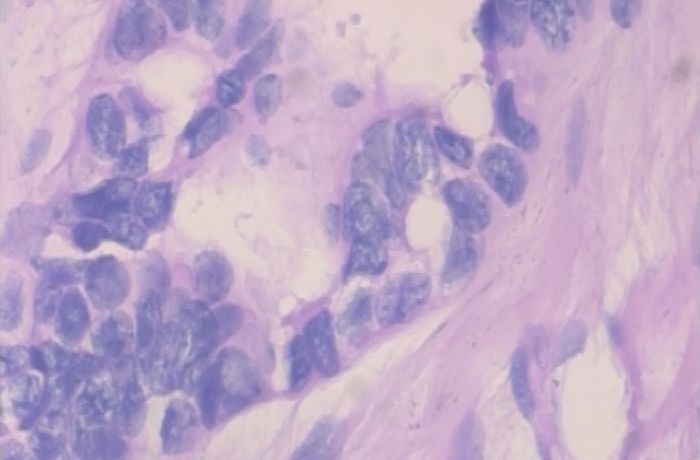

以上两张图片是恶性样本